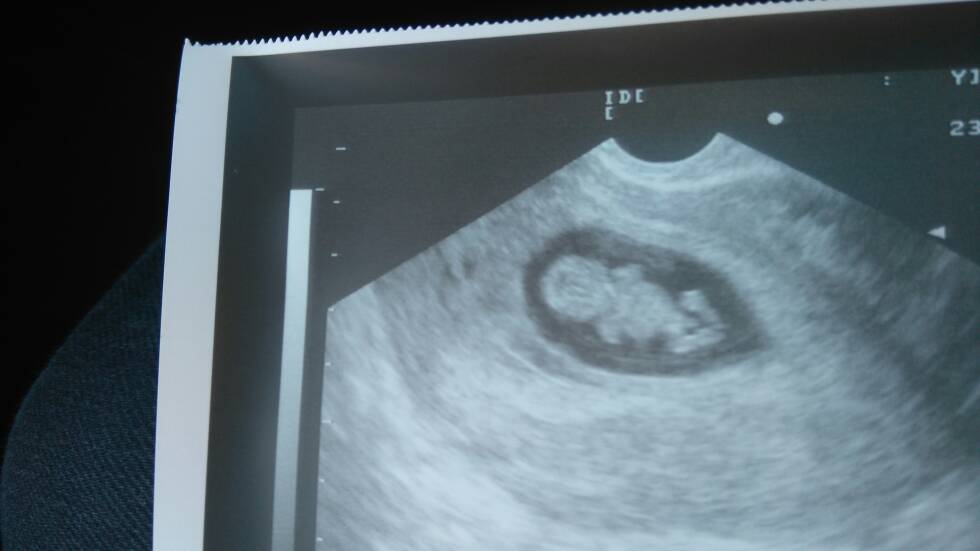

Śliczne te nasze maluszki, a to mój, kurcze coś mu dynda między nogami, też to widzicie?

Choć mam nadzieje ze to pepowina, bo marzę o córeczce :-)

Zobacz załącznik 776457